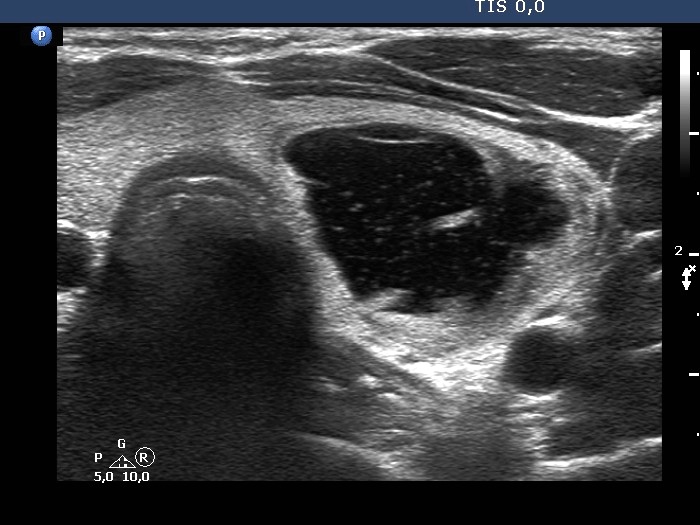

Second examination 4 years later (second and third rows of images):

Clinical presentation: The patient had no complaints.

Palpation: unchanged.

Result of blood test: TSH 1.52 mIU/L.

Ultrasonography. The cystic nodule had refilled. The presentation remained the same.Seven mL brown fluid was aspirated. Cytology: benign, cystic lesion.

Suggestion: ultrasound in two years.